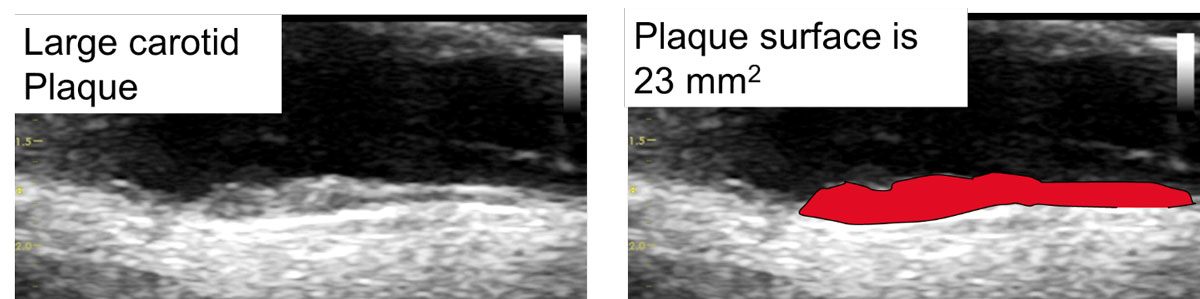

Figure 2 shows the measurement of a plaque area through tracing the longitudinal surface of a carotid plaque (23 mm2). A plaque area of 23 mm2 corresponds to a vascular age of 34 years in men and 43 years in women. VA70 corresponds to a total plaque area of 108 mm2 in men and 66 mm2 in women. This represents high risk atherosclerosis: VA70 = 99th percentile for men (sensitivity 9%, specificity 97%) and 99th percentile for women (sensitivity 18%, specificity 95%) in the Tromsø study (n = 6226, with follow up of 6 years, 297 myocardial infarctions during follow up [2]. Bayes post-test risk [23] of VA70: for 4% AGLA 11% in men, 13% in women; for 10% AGLA: 25% in men and 29% in women. Therefore, VA70 transforms low into intermediate and intermediate into high cardiovascular risk.

Figure 2 Vendor independent easy to perform measurement of TPA using the surface tool, resulting in an area of 23 mm2, which would correspond to an vascular age of 34 years in men and to an vascular age of 43 years in women. VA70 corresponds to a total plaque area of 108 mm2 in men and 66 mm2 in women, indicating advanced carotid atherosclerosis.